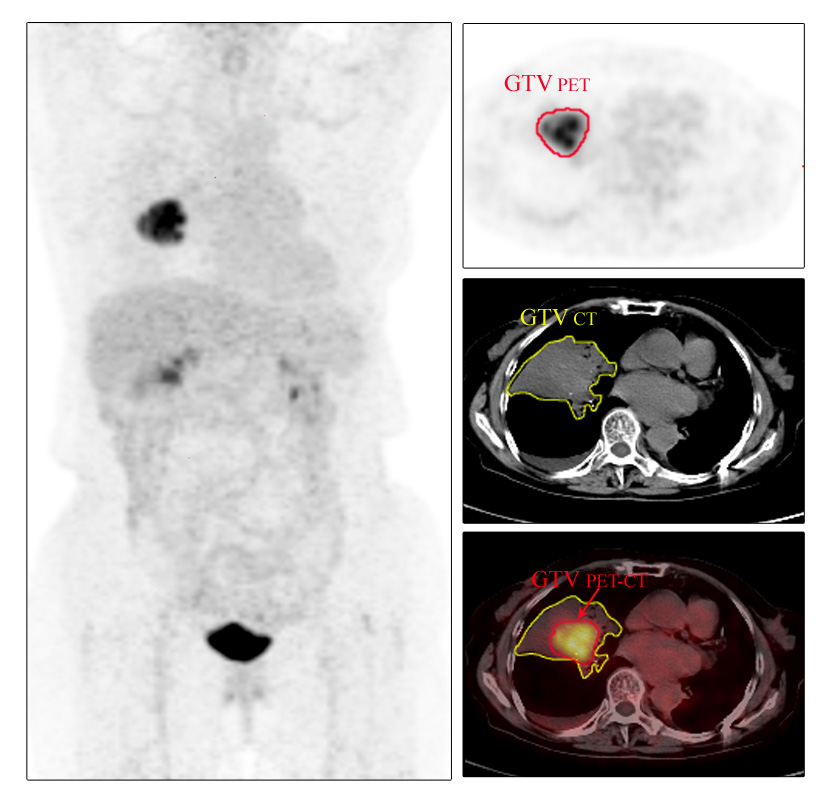

病例三 放疗精确定位患者,女,84岁,咯血半年多,全身PET-CT扫描示:右肺中叶近肺门处见软组织肿块影,边界欠清,右肺中叶支气管闭塞,其远端可见大片密度增高影及含气支气管影,前述肿块放射性摄取异常增高,SUVmax=10.9,考虑右肺中叶肺癌伴远端阻塞性肺不张,拟行放疗,生物靶区勾画如上图所示,可以看出在PET-CT的帮助下,其勾画的靶区较CT更加精准,从而避免了其邻近的不张肺组织接受不必要的照射。